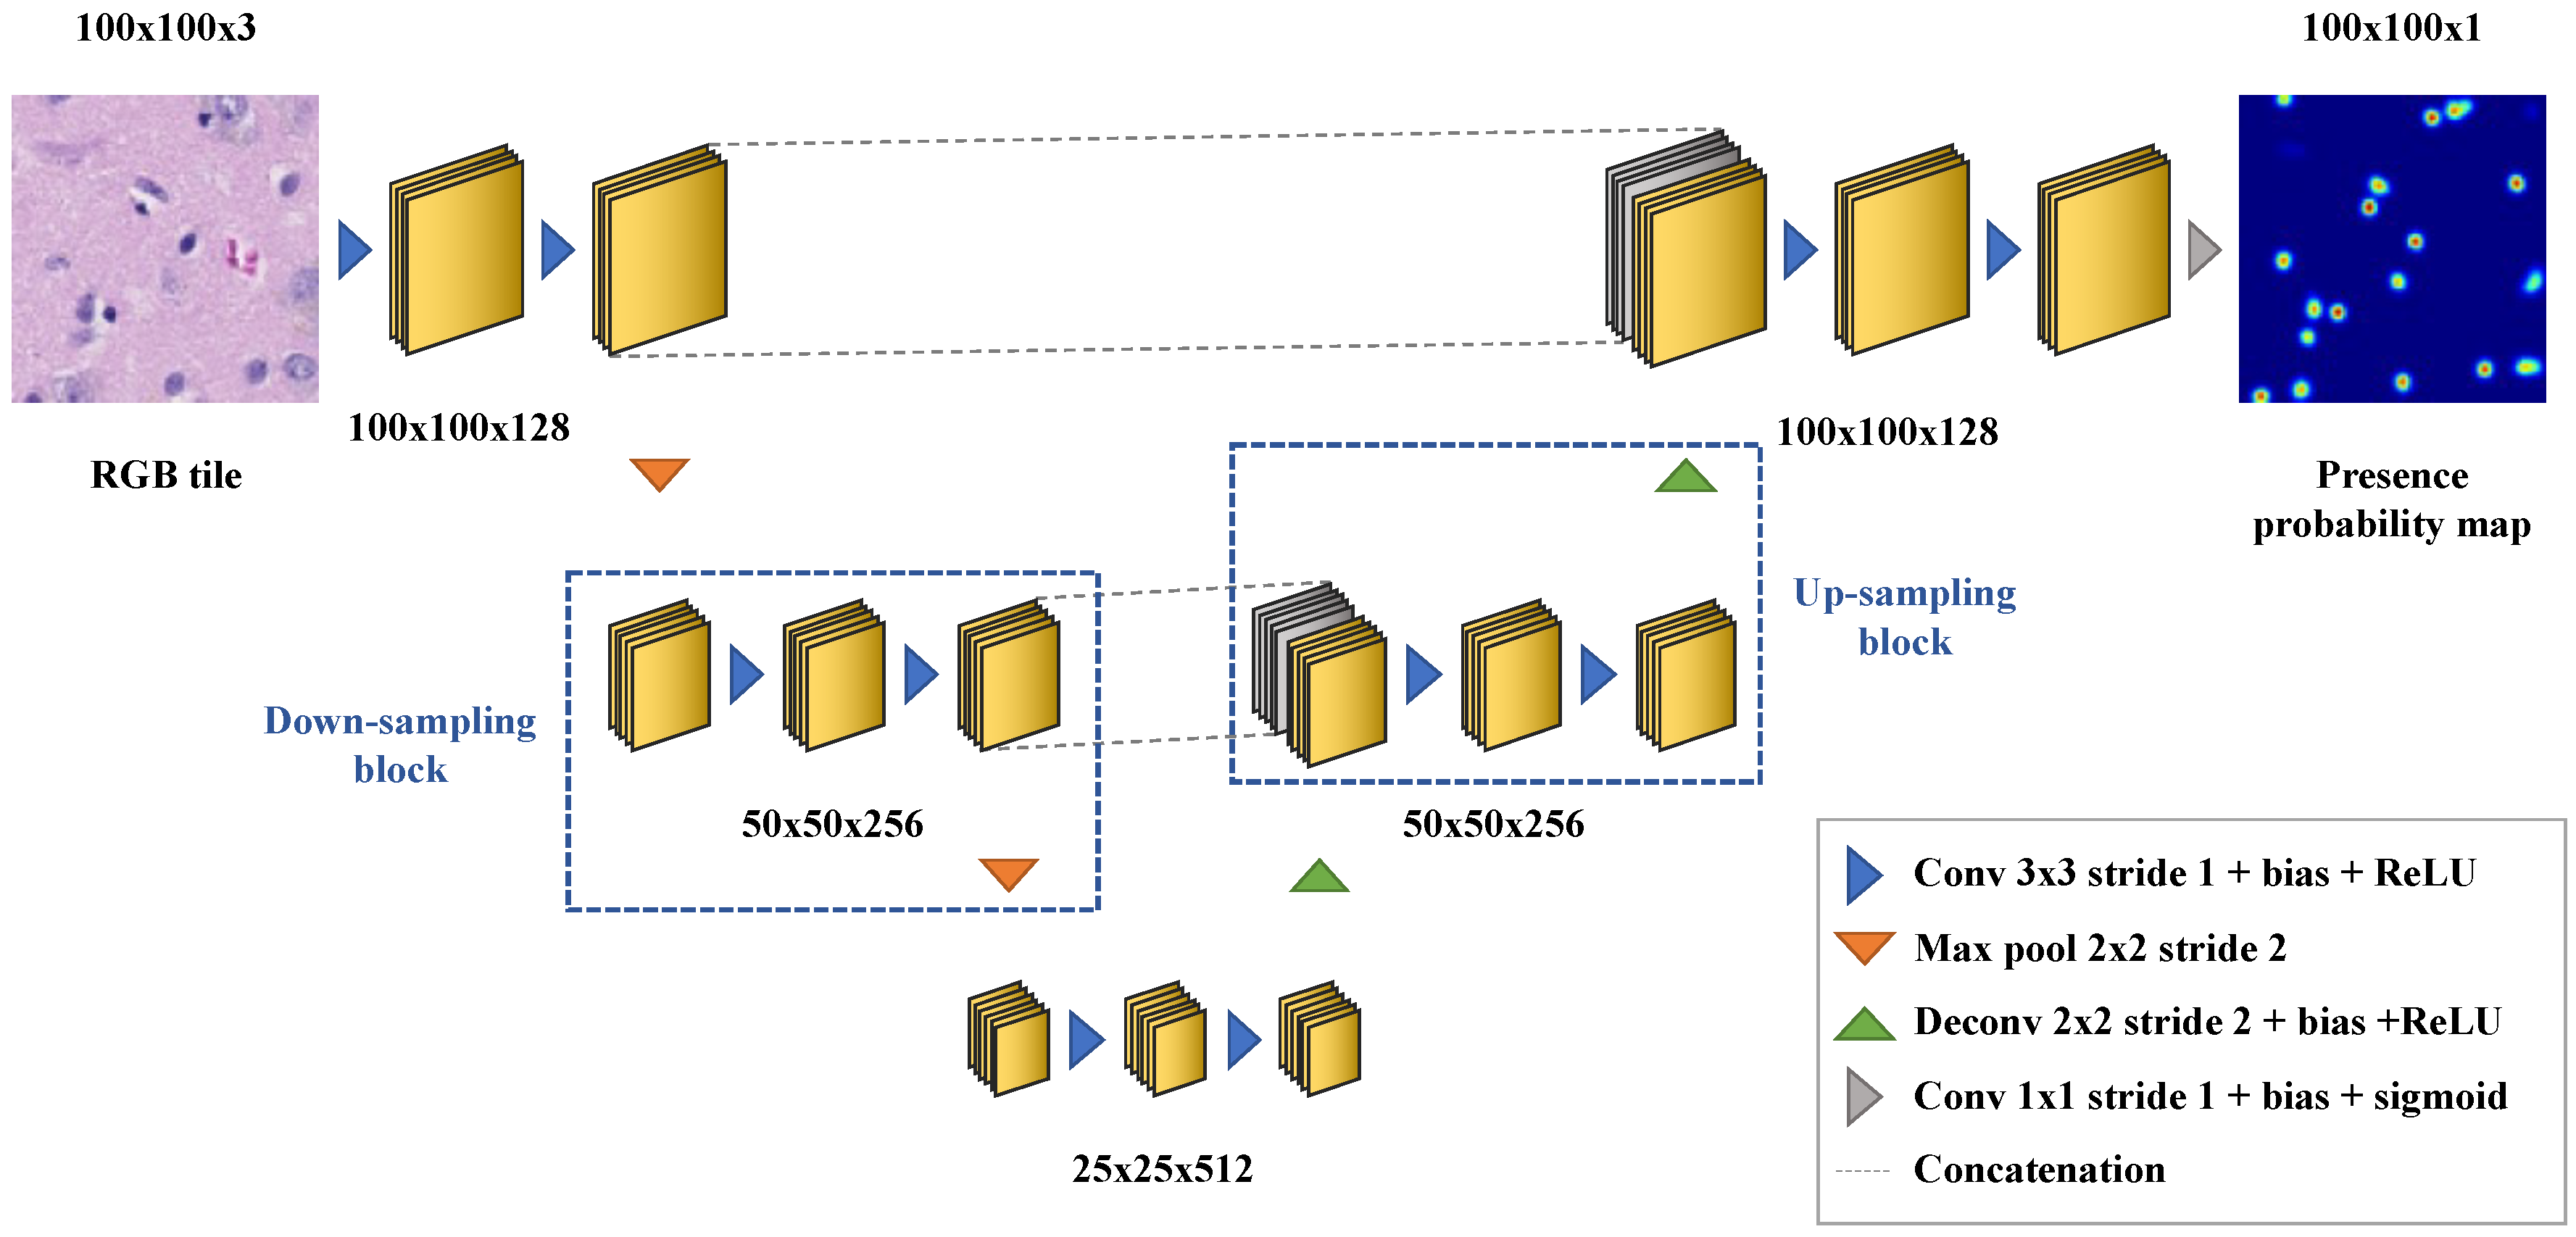

2.5. Cell Density Maps

Appendix B. Deep Learning-Based Nuclei Counting